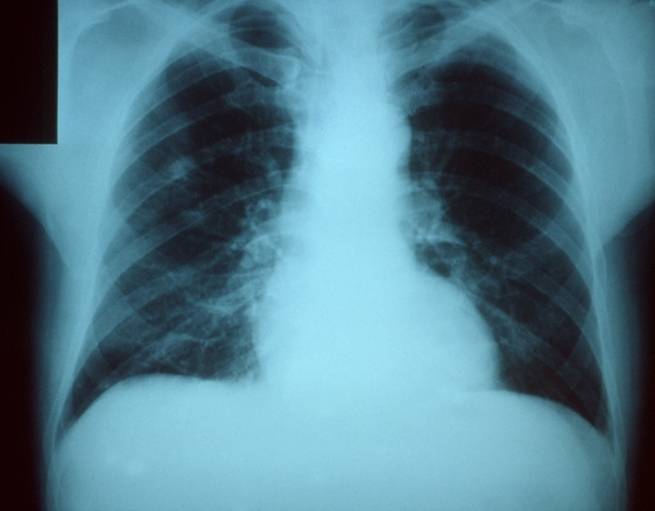

ففي الرئتين على سبيل المثال، يمكن للتورم أن يمنع الأكسجين من الوصول إلى الأوعية الدموية. فالأكسجين ينتقل عادةً عبر الأغشية الرقيقة جداً في عدد كبير من الأسناخ الرطبة داخل الفصوص الرئوية. وعندما يتورم هذا النسيج بسبب الخلايا المناعية، يصبح من الصعب على الأكسجين الوصول إلى الأوعية الدموية الصغيرة التي من المفترض أن ينتقل إليها. ويكون هناك أيضاً بعض الأضرار في أنسجة الرئة. ولا يمكن للفيروسات أن تتكاثر من تلقاء نفسها، ولذلك تضطر للقيام بذلك داخل خلايا الجسم. وهذا يعني بأنه من أجل قتل الفيروس، فإن على جهاز المناعة تخريب الجسم إلى حد ما، الأمر الذي يجعل عملية الأكسجة أصعب.

ويُذكر بأن حوالي ثلث الناس الذين يموتون من الإنفلونزا يموتون مباشرة. أي أنهم يموتون من آثار الفيروس (والآثار الناجمة عن محاولة أجسادهم مكافحة الفيروس). ويعدّ الفشل التنفسي – عندما لا تتمكن الرئتان ببساطة من الحصول على ما يكفي من الأوكسجين – هو أحد الطرق الأكثر شيوعاً، كما أنه أحد أسرع هذه الطرق. وتحدث الوفيات المباشرة من الإنفلونزا بسرعة، وغالباً في غضون أيام قليلة، ويرافقها القليل من علامات التحذير.

ولكن عندما يكون الجهاز المناعي مضطرباً بالفعل تحت تأثير العدوى الفيروسية، فيمكن أن تنتشر هذه البكتيريا إلى الرئتين وتقوم بالسيطرة. وهذا ما يسمى بالعدوى الثانوية، ونسميها عندما تحدث في الرئتين بالالتهاب الرئوي. وعلى عكس الموت المباشر، يعمل الالتهاب الرئوي الثانوي ببطء أكثر. سوف تبدأ غالباً بالشعور على نحو أفضل بعد بضعة أيام من الإصابة بفيروس الإنفلونزا عندما يبدأ جسمك بمحاربته بشكل أكثر فعالية. وبعد ذلك، تشعر فجأة بأنك أسوأ بكثير. حيث تكون البكتيريا قد استغلت الوقت وأصبحت تتكاثر بسرعة داخل الرئتين، ويصبح جهاز المناعة المضطرب بالأصل يكافح من أجل المواجهة.